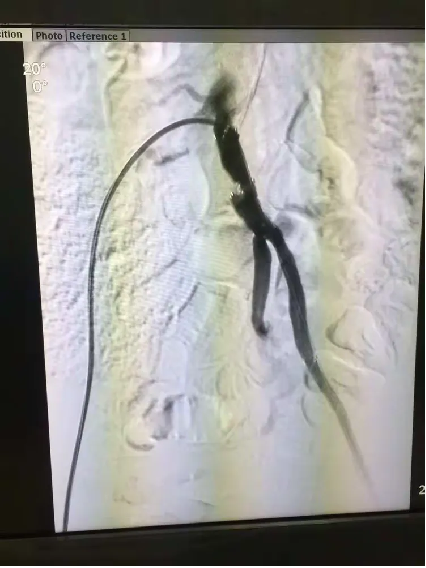

手术中,团队操作沉稳有序:导丝在闭塞血管中精准探路,球囊逐级扩张狭窄段,支架随后稳稳释放。整个过程如行云流水,医护人员配合默契,未见半分忙乱。“血流恢复了!” 监测仪器上跳跃的数据,宣告着双侧“生命线”的重建成功。